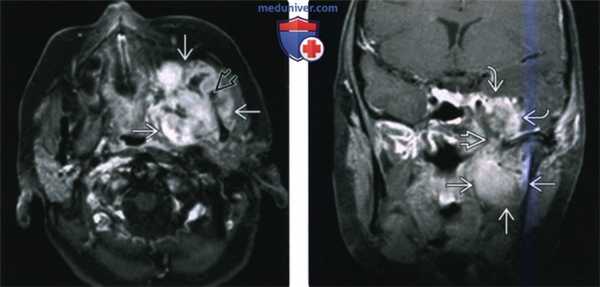

(Слева) МРТ Т1ВИ FS с КУ, аксиальная проекция. Лейомиосаркома жевательного пространства высокой степени злокачественности. Опухоль неоднородно накапливает контраст и прорастает в нижнюю челюсть. Только по данным лучевой диагностики дифференцировать различные типы сарком невозможно, за исключением случаев обнаружения матрикса остео- или хондросаркомы.

(Справа) МРТ Т1ВИ FS с КУ, коронарная проекция, тот же пациент. Новообразование, накапливающее контраст, распространяется в полость черепа через овальное отверстие. Отсюда опухоль может прорастать в пещеристый синус.

(Слева) МРТ Т1ВИ в аксиальной проекции. Саркома Юинга, локализующаяся в жевательном пространстве. Обратите внимание, что сигнал относительно здоровых мышц гиперинтенсивный. Нижняя челюсть разрушена, определяется лишь небольшой ее фрагмент. Жировая клетчатка окологлоточного пространства смещена в медиальную сторону.

(Справа) МРТ Т2ВИ FS, аксиальная проекция, тот же пациент. Неоднородный сигнал высокой интенсивности. Крупный лимфоузел в заглоточном пространстве слева представляет собой случайную находку.

(Слева) На аксиальной МРТ (Т1 ВИ C+) в жевательном пространстве визуализируется лейомиосаркома высокой степени злокачественности, неравномерно накапливающая контраст и поражающая нижнюю челюсть. Большинство типов сарком жевательного пространства сложно дифференцировать в отсутствие костного или хондроидного матрикса.

(Справа) На корональной МРТ (Т1 ВИ С+ FS) у этого же пациента визуализируется контрастирующаяся опухоль с интракраниальным распространением через овальное отверстие а и поражением кавернозного синуса.

(Слева) На аксиальной МРТ (Т1ВИ) в жевательном пространстве визуализируется саркома Юинга в виде огромного объемного образования с гиперинтенсивным относительно мышц сигналом. Ветвь нижней челюсти разрушена, на этом изображении виден лишь ее мелкий фрагмент. Полоска окологлоточного жира смещена кнутри.

(Справа) На аксиальной МРТ (Т2ВИ FS) у этого же пациента определяется неоднородный сигнал крайне высокой интенсивности в опухоли. Хорошо различимый заглоточный лимфоузел слева является случайной находкой.